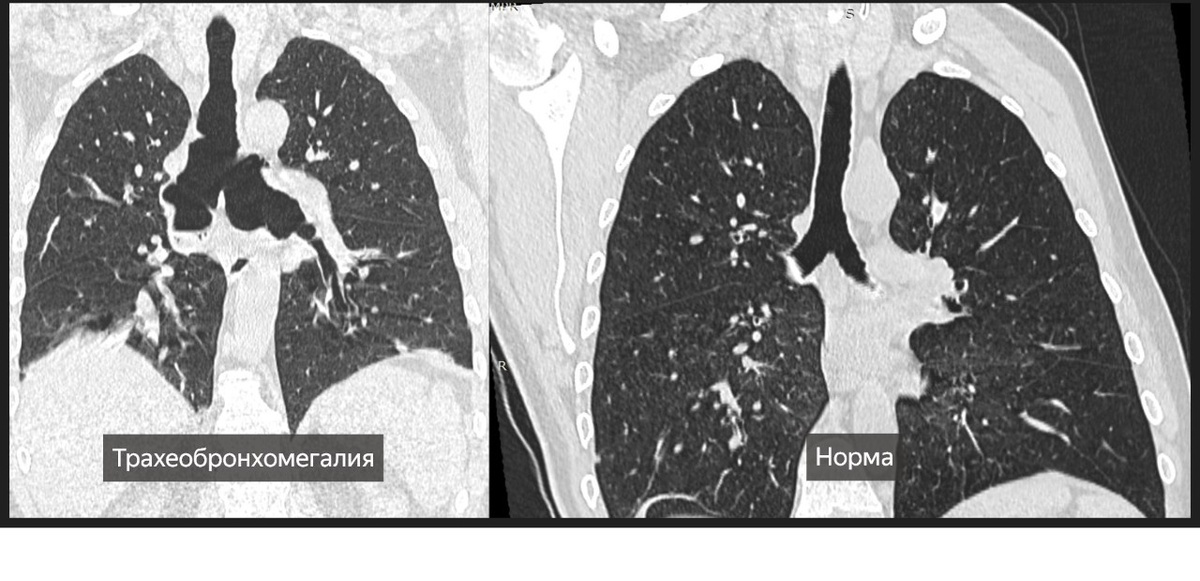

На КТ грудной клетки выявлены: ателектаз, скопление секрета в бронхах и трахеобронхомегалия — ключевой признак синдрома Мунье–Куна. Такое расширение трахеи и крупных бронхов делает пациента уязвимым к частым инфекциям дыхательных путей.

Так, в этом году в Ильинскую больницу поступил пациент с заболеванием, известным в медицине преимущественно по единичным описаниям — синдромом Мунье–Куна (трахеобронхомегалией).